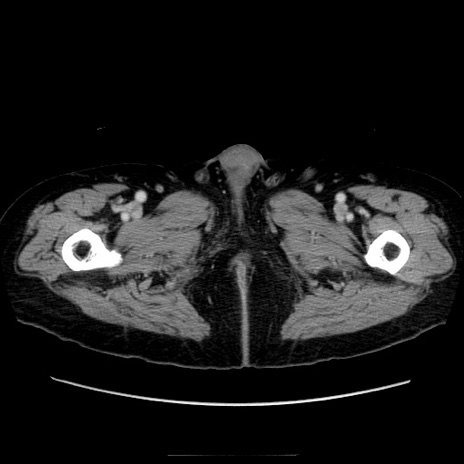

症例21(横断像)

【症例】70歳代男性

【主訴】腹痛

【現病歴】肝硬変・肝細胞癌にてかかりつけの方。約9時間前に食後より腹痛出現。症状が徐々に増悪し、嘔吐出現したため来院。

【既往歴】肝硬変、肝細胞癌(RFA、TACE後)

【身体所見】意識清明、表情苦悶様、BT 36℃、BP 129/78mmHg、P 88bpm、SpO2 97%(RA)、右上腹部から心窩部にかけて圧痛あり、反跳痛なし、筋性防御あり。

【データ】WBC 5800、CRP 0.16